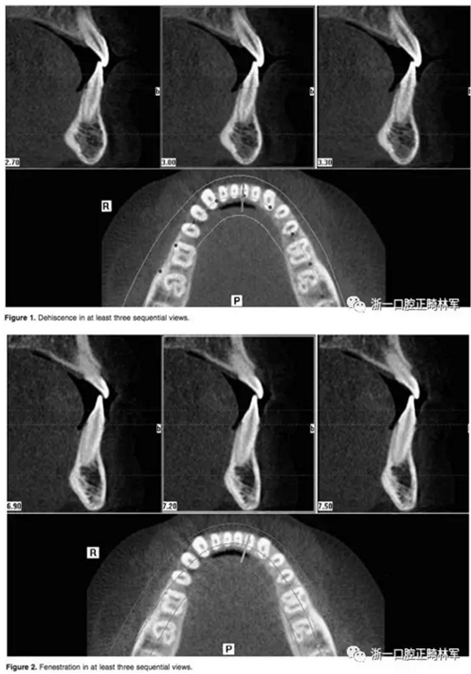

在iCAT配套軟件上進(jìn)行數(shù)據(jù)的二次三維重建。這種二次重建能夠創(chuàng)建最大精度的三維圖像使我們能夠進(jìn)行線性測量。每根牙根在軸向和橫斷面的切片上進(jìn)行距離頰舌側(cè)牙槽骨距離的評估。在至少三個連續(xù)的視圖中,牙根周圍沒有皮質(zhì)骨的情況被認(rèn)為是牙根周圍存在牙槽骨缺損。如果牙槽骨高度低于釉牙骨質(zhì)界超過2毫米,記為骨開裂。如果牙槽骨的缺損位于牙槽嵴下方而未至牙槽嵴頂,記為骨開窗。